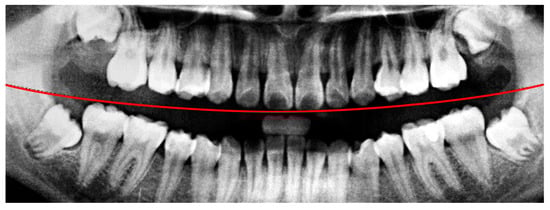

In the framing adjustment step, the central point of the oral structure was first identified. This point corresponded to the vertex of a second-order polynomial curve. The gap between the upper and lower jaws was then modeled using a quadratic curve that passes through the central point and connects to two boundary points on the image frame [21], as described by Equation (1). The resulting second-order curve used to represent the jaw separation is shown in Figure 4.

Figure 4. The result of the curve and central point are labeled. The red line indicates the boundary between the upper and lower jaws (maxilla and mandible) in this study.